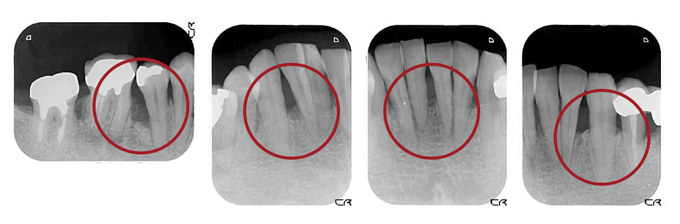

BEFORE(初診時)

赤丸の黒く抜けている部分は歯周病により骨が失われています。

AFTER ( 術後:歯周組織再生療法 )

赤丸の部分に骨移植を行って術後10ヵ月程たった状態です。

黒い部分が白くなってきています。骨が少しずつできてきています。

最初は抜かなければならない可能性の歯もこのように再生療法によって、残す事が可能となります。